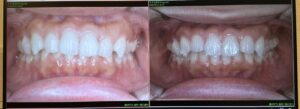

矯正前(左)では、前歯が少し重なって見え、歯の並びがデコボコしていました。

一方、矯正途中(右)では、歯が横一列に近づき、ガタつきが明らかに減ってきているのがわかります。

大きな変化ではないように見えて、毎日自分の口を見ている身としては、確実な前進を感じています。